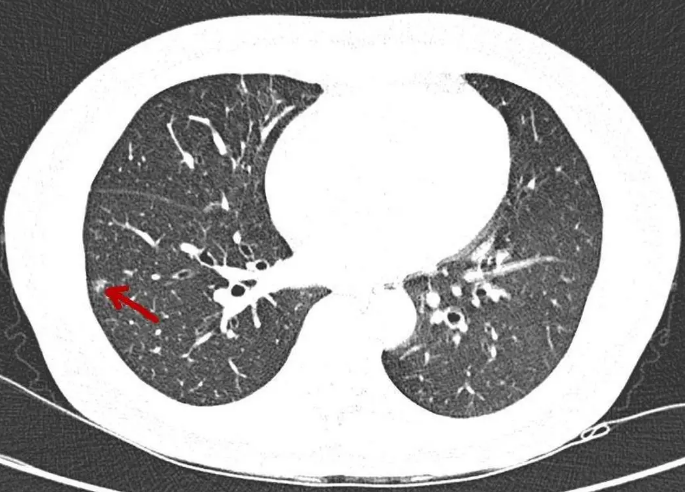

这里有必要清楚关于肺部结节的概念,其实只要在体检的时候发现肺部上出现了跟正常肺部组织不一样的结节影,那么在报告单上都会出现“肺结节”,一般大于两厘米以上的肺部结节医生会称为“肿物”,而小于两厘米的则称为“肺结节”,其实有很多人在体检的时候都会发现肺部结节,但是有百分之九十五以上的都是良性的,特别是如果肺部结节的直径小于五毫米的都是良性的。

有肺癌的患者,在早期也会出现肺结节,所以可以发现,有很多原因会导致肺结节的出现,并不是只有肺癌才会发现肺结节,而且肺结节也并不一定就会变成肺癌。